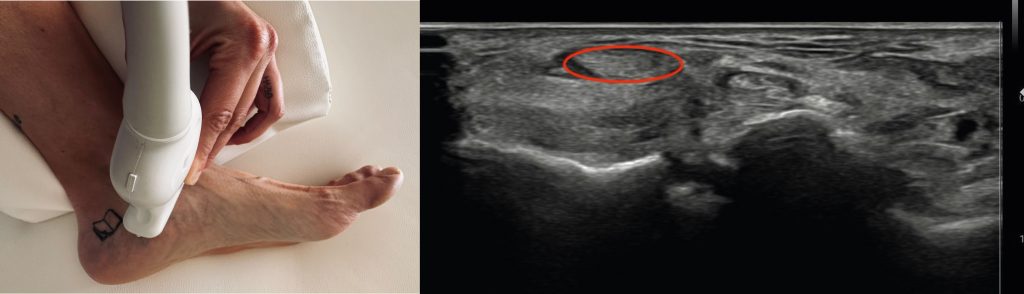

El tipo de corte que estudiaremos es el siguiente:

Para hacer correctamente una ecografía del tendón del tibial posterior necesitas tener al paciente en decúbito supino con ligera rotación externa de cadera. El tendón del tibial posterior está señalado en rojo en la imagen de arriba.